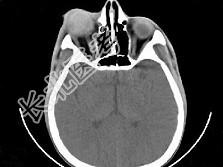

- 单项选择题女,24岁, 发热畏寒数天,右眼睛疼痛, PE:右眼睑肿胀, 结膜充血,伴右眼突出, CT如图所示,最可能的诊断是 ( )